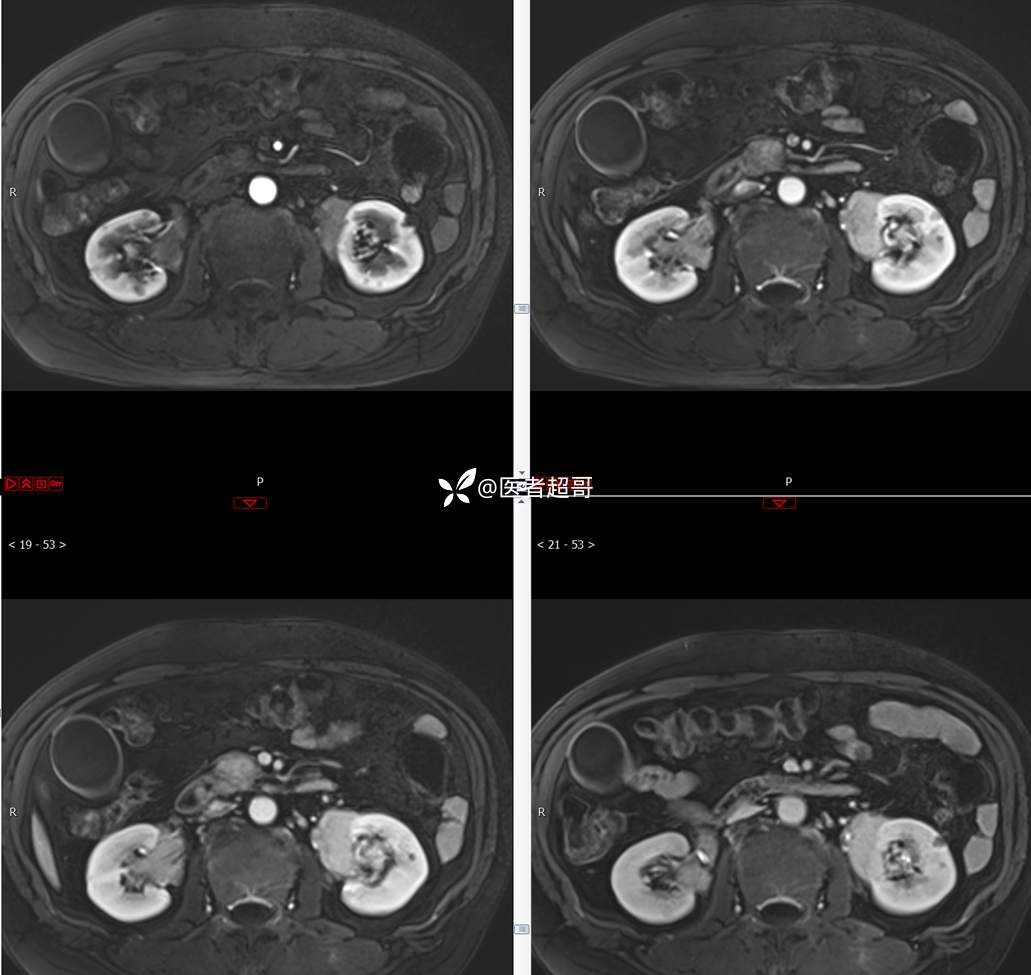

【影诊笔记772】腹痛就诊,发现肾脏病变,CT、MRI齐全,请高诊!

男,63岁 0200825 01

主 诉:间断腹痛15天

现病史:患者15天前无明显原因及诱因出现腹部疼痛不适,呈间断性钝痛,右下腹为著,无尿频、尿急、尿不尽,无发热、寒战,无腹胀。于市中心卫生院住院治疗,超声示:胰头低回声包块,胆系扩张,左肾囊肿,胆囊壁毛糙,胆囊内胆汁淤积。患者为求进一步诊治,遂以“肾盂肿瘤”收入院,患者自发病以来,神志清,精神可,饮食睡眠可,大便无明显异常,近期体重无明显增减。

既往史:既往体健